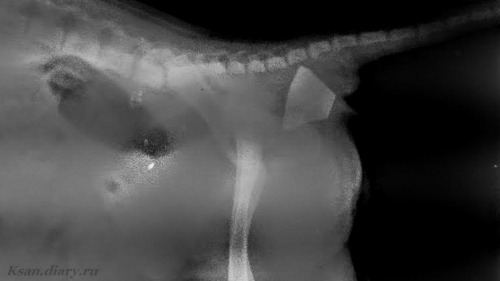

6) Вынужденная поза и беспокойство. Если собака все время меняет положение, ложится и сразу встает, ходит, ищет место, снова ложится и встает - значит ее что-либо беспокоит. Бывает, при болях в определенных областях, собаки принимают вынужденную позу: например, сгорбленная спина - признаки боли в брюшной полости. Так же признаком беспокойства может быть хождение по кругу, хаотичные движения. Собака может с трудом или неохотно ложиться или вставать, отказаться запрыгивать на диван.

Хотя, в некоторых случаях не стоит забывать о разнообразии пород (строение черепа, количество кожи и породная мимика) и о том что собаченьки те еще артисты. Я пробую показать несколько довольно ярких примеров, но их действительно не очень много. Как оказалось, кошек я фотографирую чаще. 🤷♀️ Тут видно, что шкалу боли для собак по мордашке составлять бесполезно.